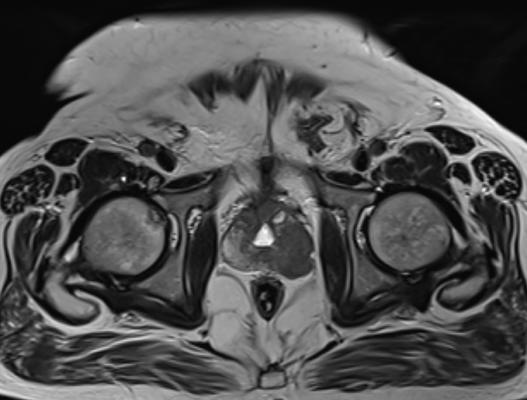

In the TULSA procedure, a small catheter-like device is inserted through the urethra into the prostate. Once there, MRI is used to guide precise positioning of 10 therapeutic ultrasound elements into the prostate. MR thermometry is used to monitor the tissue while heating to more than 55 degrees within the prostate and limiting heat to the sensitive nerves surrounding the prostate as the device rotates around the entire gland. The procedure can be performed in an outpatient or in-patient facility under general or spinal anesthesia in two to three hours.

In the prospective observational study, participants showed improvement in the reduction of the presence of cancer, prostate size and prostate-specific antigen levels (PSA), which are markers for cancer. Cancer was undetectable on follow up biopsy by 76% at one year after TULSA with a decrease in median prostate volume by 92% within one year and a decrease in PSA from 6.3 ng/ml to 0.63 ng/ml at five years.